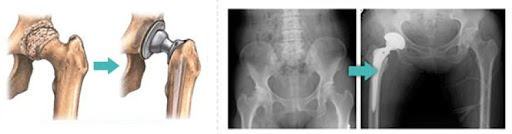

- 인공관절 치환술: 가장 일반적인 고관절 수술입니다. 퇴행성 관절염이나 심한 외상으로 인해 고관절이 손상된 경우, 인공 관절로 대체합니다. 이 수술은 대개 1-2시간 가량 소요되며, 회복이 길어질 수 있습니다.

각 수술 방식에 따라 환자의 상태를 고려한 특화된 치료 계획이 필요합니다. 예를 들어, 인공관절 치환술을 받을 경우에는 십여 주의 회복 기간 동안 물리 치료와 약물 치료가 반드시 포함되어야 합니다. 반면 관절경 수술의 경우에는 초기 회복 단계에서의 가벼운 운동과 체중 부하가 더 강조될 수 있습니다.